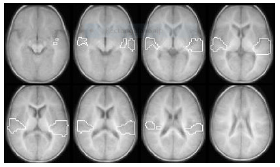

Figure 3 shows the statistical parametric map (composite Z-score map) for group activation (corrected p < 0.05) for story processing vs. silence contrast across the entire normal hearing (NH) group (n=22). Similar to our previous reports on story processing in older and awake children, the superior temporal gyrus (STG) is activated in the NH group [22]. As tabulated in Table 2, the group analysis [with the generalized linear model (GLM)] also detected activation in the visual cortex for sedated infants with normal hearing (NH).

Figure 3: Composite Z-score maps (in axial plane) showing significantly activated brain regions (p < 0.05) during language processing (across the slice range 2.5 to +37.5 mm) for the story vs. silence contrast in (a) the normal hearing (NH) control group (n=22) and (b) the hearing impaired (HI) group [less than 24 months of age (n=11)]. (c) Group difference map for the story vs. silence contrast across the NH and HI subjects (p < 0.05). Red indicates areas where activation in the HI group is greater compared to the NH group. Blue indicates areas where the NH group show greater activation compared to the NI group. Tables 2 and 3 include activated brain regions in figures (a) and (b).

We used the stories vs. silence contrast in the HI group (n=11) to construct the composite Z-score map shown in Figure 3b. Although HI infants demonstrated lower BOLD activation in auditory and language areas (in response to speech stimuli) than the NH group, consistent bilateral activation is seen in the middle and superior temporal gyri (BA21 & 22), the transverse temporal gyrus (BA41), and Heshl’s Gyrus (Figures 3a & 3b). The activated brain regions in the HI group are tabulated in Table 3, including Brodmann’s Area designations, anatomical regions, and normalized coordinates in the CCHMC 76 framework [15].

To better visualize differences between the NH and HI groups, we computed the statistical difference map between groups for the stories vs. silence contrast (Figure 3c). Red areas indicate regions where the HI group had significantly higher activation (p < 0.05) compared to the NH group. Similarly, areas where the activation in the NH group is higher than the HI group are shown in blue (p < 0.05).